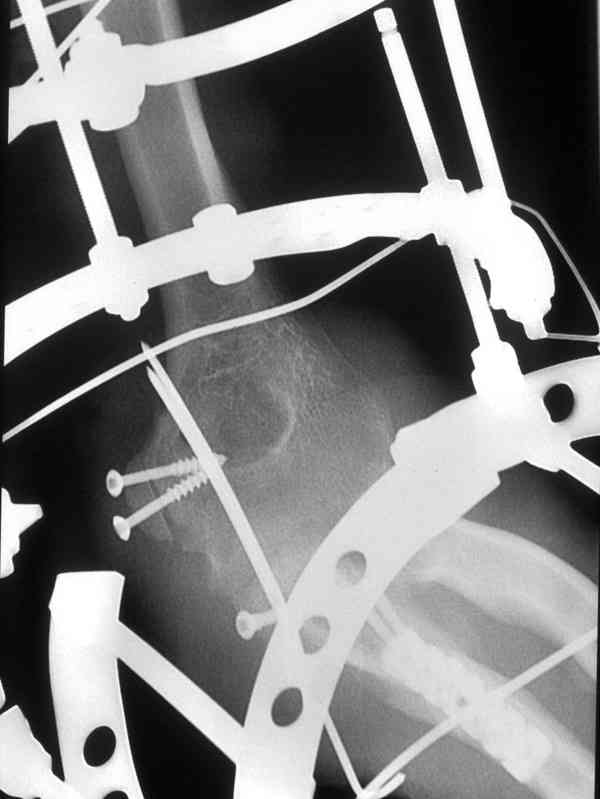

Больной был прооперирован.Протеза головки лучевой у нас нет. Решили с локтевой костью пока ничего не делать. Выполнили операцию по востановлению связочного аппарата локтевого сустава(см.схему)- модфикация метода W.E.Spring,сухожилие мы фикстровали к винту на локтевой.

Естественно ревизия сустава и удаление рубцово-хрящевидных тканей.Затем наложили аппарат Илизарова с шарнирами. Первые 2 дня сустав был фиксирован трансартикулярно 2-мя спицами, затем спицы удалили. И больной начинает движения в аппарате.

Прилагаюся послеоперационные рентгенограммы.

Планиуем аппарат на 3-4 нед.